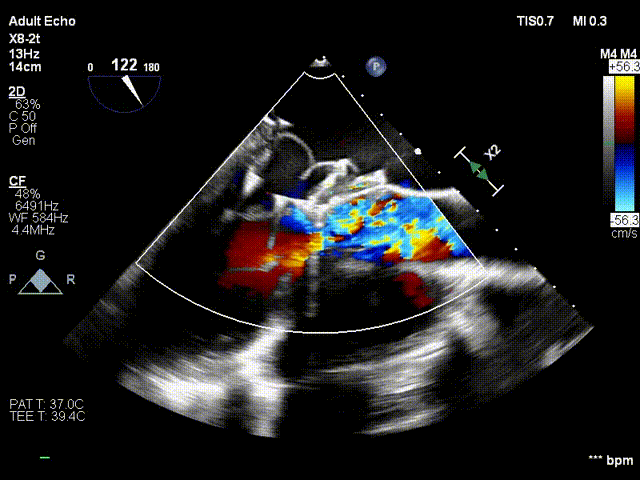

术前心超二尖瓣重度反流

术中超声瓣膜定位

术后复查心超二尖瓣反流消失